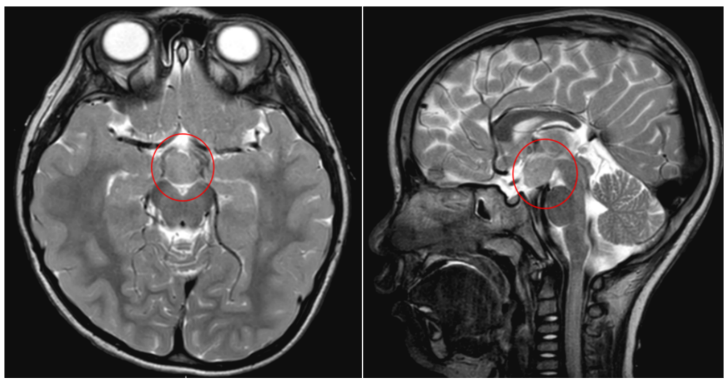

该院神经外八科二区(癫痫外科)副主任陈俊喜接诊后,与癫痫中心团队联合会诊,根据检查结果,诊断患儿为下丘脑错构瘤引发的痴笑样癫痫。“患儿的‘哭闹’表情,其实是痴笑样癫痫的表现。”陈俊喜介绍道。

在手术机器人辅助下,陈俊喜带领团队为患儿进行了立体定向脑电图(SEEG)微创置入手术,将6根电极精准置入患儿颅内瘤体,确定放电核心位点后进行微创热凝毁损治疗,解决患儿癫痫发作的情况。